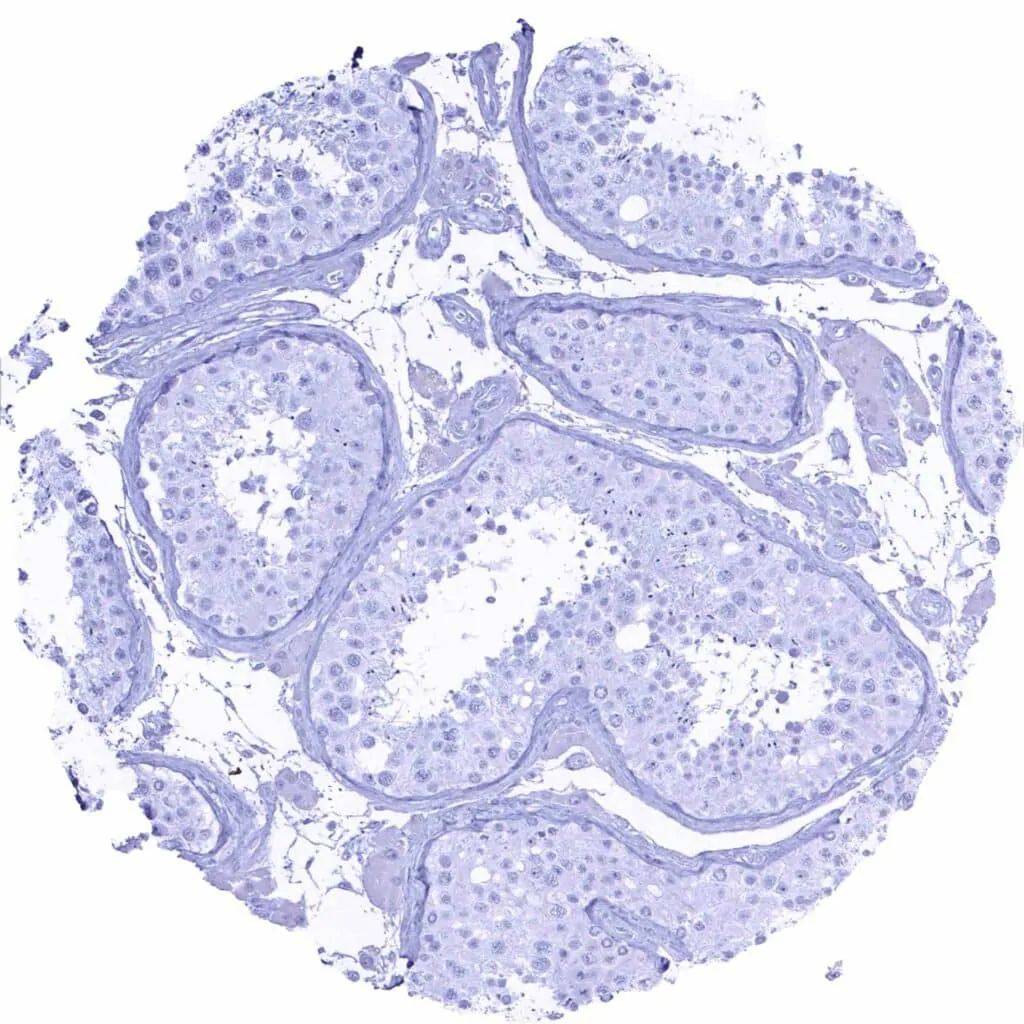

Testis